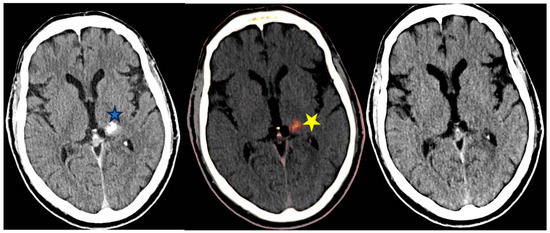

5.5. Examples in Neuroradiology

Post Endovascular Thrombectomy (EVT)